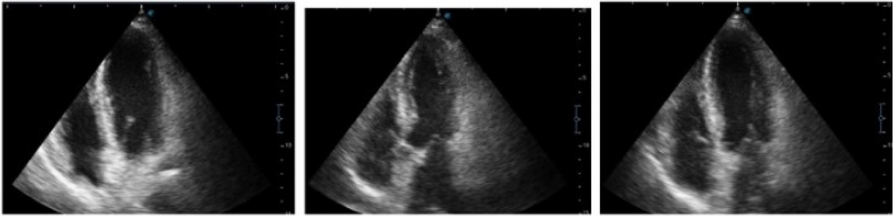

In this specific case, the patient, affected by L. Pneumophila, presented a PO2/FiO2 ratio between 100mmHg and 200mmHg, giving rise to a moderate ARDS panel according to Berlin Criteria (Image 1).

For this reason, we decided to use a non-invasive periprocedural ventilation mode, specifically the High Flow Nasal Cannula (HFNC), to reduce the risk of postoperative pulmonary complications due to invasive ventilation through endotracheal intubation (ETI).

The parameters set during the entire procedure remained stable: Flow 60 L/min, FiO2 100%, Temperature 37 °C.

The patient, opportunely mixed with the current type of anesthesiological procedure and immediately after signing the Informed Consensus, is premedicated with intravenous Midazolam 0.05mg/Kg, while sedation is effected with an initial bolus of Propofol at 0.5mg/Kg. Successively, sedation is maintained whit Propofol in continuous infusion at 3.5mg/Kg/h.

The approximate duration of the procedure is 25 minutes. The patient's vital parameters are stable for all the duration of the intervention, with a SpO2 > 95%, and a MAP > 70 mmHg.

After the procedure, the patient is returned to the Intensive Care unit where he has completed the course of antibiotic therapy, with a progressive reduction of the need for oxygen therapy.